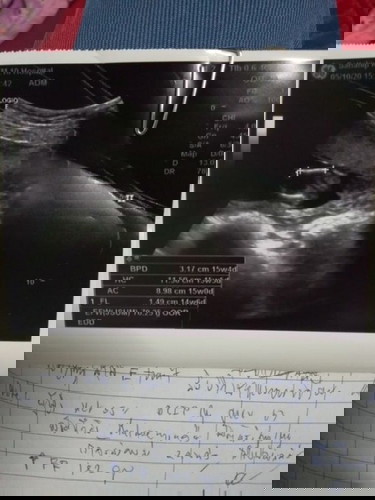

#ท้องแรกคะ เพิ่งไปซาวด์มา หมอบอกรกหนามาก ไม่สามารถคลอดเองได้ต้องผ่าอย่างเดียว กังวลมากค่ะ แม่ท่านไหนรกหนาเหมือนกันบ้างคะ